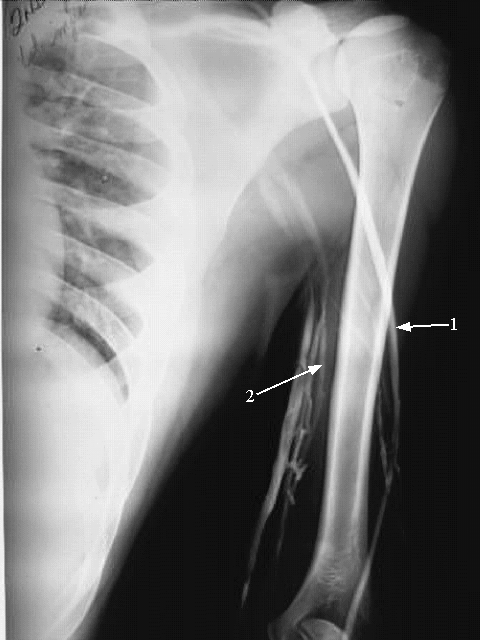

Upper Limbs:Upper Limb Venogram:

1. Cephalic Vein

2. Basilic Vein.